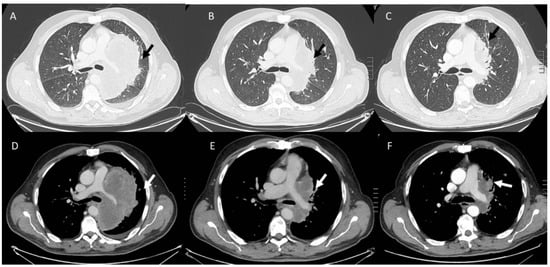

- Kalisz, K.R.; Ramaiya, N.H.; Laukamp, K.R.; Gupta, A. Immune Checkpoint Inhibitor Therapy-related Pneumonitis: Patterns and Management. Radiographics 2019, 39, 1923–1937. [Google Scholar] [CrossRef] [PubMed]

- Wang, G.X.; Kurra, V.; Gainor, J.F.; Sullivan, R.J.; Flaherty, K.T.; Lee, S.I.; Fintelmann, F.J. Immune Checkpoint Inhibitor Cancer Therapy: Spectrum of Imaging Findings. Radiographics 2017, 37, 2132–2144. [Google Scholar] [CrossRef]

- Kwak, J.J.; Tirumani, S.H.; Van den Abbeele, A.D.; Koo, P.J.; Jacene, H.A. Cancer immunotherapy: Imaging assessment of novel treatment response patterns and immune-related adverse events. Radiographics 2015, 35, 424–437. [Google Scholar] [CrossRef]

- Borcoman, E.; Kanjanapan, Y.; Champiat, S.; Kato, S.; Servois, V.; Kurzrock, R.; Goel, S.; Bedard, P.; Le Tourneau, C. Novel patterns of response under immunotherapy. Ann. Oncol. 2019, 30, 385–396. [Google Scholar] [CrossRef]